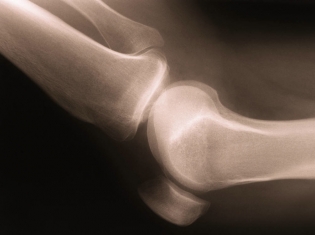

A recent study looked at the role race and gender played in the risk of developing knee OA. Knee OA is a degenerative disease of the knee joint.

The study found African American women were at a higher risk for knee OA and total knee replacement (TKR) than other sex and race combinations.